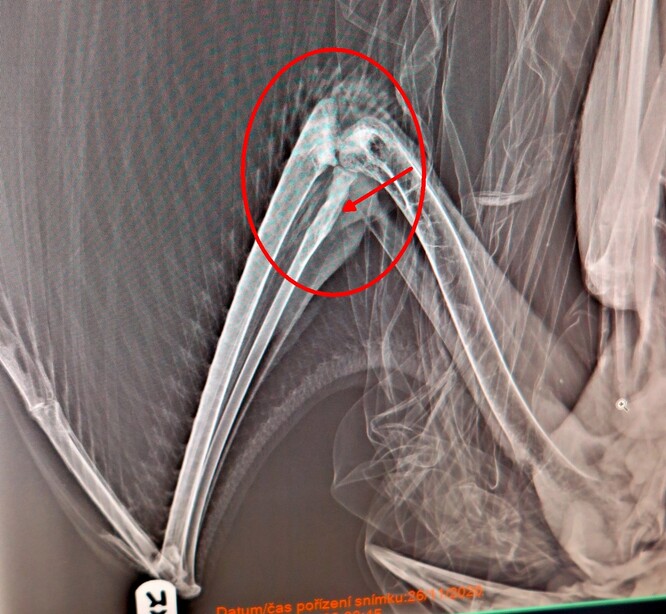

Jelikož se jedná o dospělého, ale výrazně menšího a lehčího ptáka (pravděpodobně samici), nebyl odchyt tentokrát takovým krveprolitím jako v případě našeho odchytu jeřába prvého. Navíc tady se prokazatelně jednalo i o odchyt částečně handicapovaného ptáka, což prokázalo i následné veterinární vyšetření a RTG snímek.

Tady si možná leckdo řekne: „No jo, odchytit poraněného ptáka dokáže každý.“ Jenže tenhle pták měl své poranění už částečně zhojené (fraktura je velice slušně srostlá) a dokonce na lokalitě už i nějakou dobu rehabilitoval. Dost možná se dokonce i jedná o jeřába, který na lokalitě hnízdil a dobře ji zná. Tomu by odpovídalo i jeho chování a trasa úniku. A když půjdeme v teoretických úvahách ještě dál, tak to může být třeba samice od samce, kterého jsme chytili a okroužkovali v srpnu. Nic z toho však není úplně podložené, samozřejmě se jedná jen o domněnky, rovněž to může být pták z první říjnové tahové vlny, který se zranil na lokalitě o všude přítomné dráty elektrického vedení a podobně.

Každopádně co ale víme úplně přesně, je skutečnost, že pták je citelně handicapovaný se zhojenou a srostlou frakturou vřetenní kosti na pravém křídle. Viditelný defekt je i v loketním kloubu a na hlavici loketní kosti. Pravděpodobně došlo i k poranění pravé nohy, přičemž doba od poranění (úrazu) se odhaduje zhruba na 4-5 týdnů s tím, že křídlo už velice pěkně skládá k tělu, ale pravděpodobně nebude už nikdy plně funkční. Plně funkční znamená, že jeřáb rozhodně nebude moci létat dálky, které jeřábi létají na zimoviště a zpět. Na druhou stranu se ale může naučit s handicapem velice slušně fungovat, a tak zatím čekáme, jak se bude vše hojit a podle toho se rozhodneme, co s jeřábem dál. Každopádně přes zimu bude muset stejně zůstat v zajetí a do jara může být situace úplně jiná.